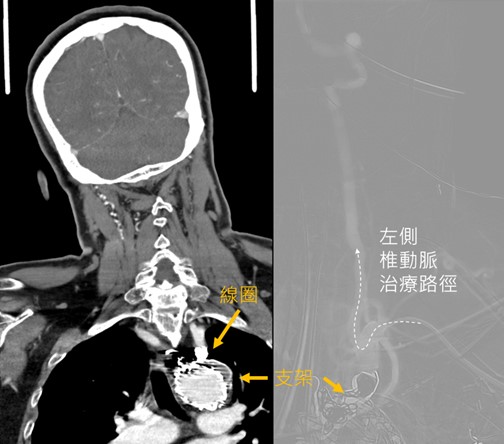

由於患者曾因主動脈剝離植入心臟支架,導致傳統取栓途徑受限。神經內科王景益醫師決定改從手臂肱動脈展開治療,並協調麻醉團隊,迅速進行取栓手術。手術過程中,取栓團隊在半小時內透過抽吸導管及支架取栓器,成功取出一條約4毫米的血栓,使病患血流恢復暢通。病患術後意識清楚,語言能力恢復正常,但短暫缺血仍影響到小腦平衡,後續由復健科協助進行肢體復健。